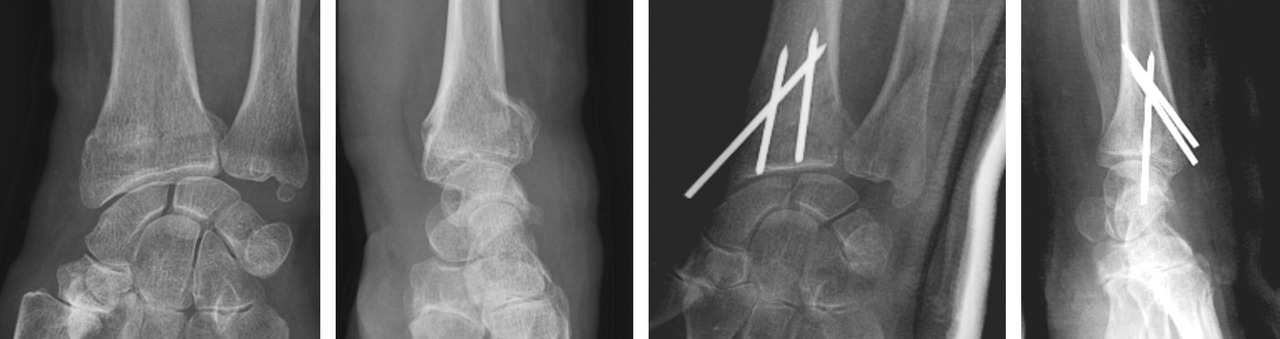

La mise en place des broches percutanées sont habituellement introduites dans le foyer de fracture, en arrière du radius, puis inclinées vers le bas pour réduire la bascule dorsale de la glène radiale et sont finalement fichées dans la corticale antérieure, épaisse, pour stabiliser la réduction obtenue. Il s’agit d’un embrochage « intrafocal » (dans le foyer de fracture). Une ou deux broches styloïdiennes dans le plan frontal complètent le montage. La bascule antérieure du fragment distal, la présence de refends articulaires, et la comminution métaphyso-épiphysaire sont indispensables à évaluer avant de proposer ce type de traitement et constituent des contre-indications relatives (fig. 12).

La mise en place de plaques palmaires nécessite un abord chirurgical antérieur et reste techniquement délicat, en particulier pour positionner la plaque en hauteur et pour la longueur des vis dont l’excès peut endommager les tendons extenseurs. L’indication phare reste les fractures métaphysaires à déplacement antérieur ou les comminutions métaphysaires étendues (fig. 13).